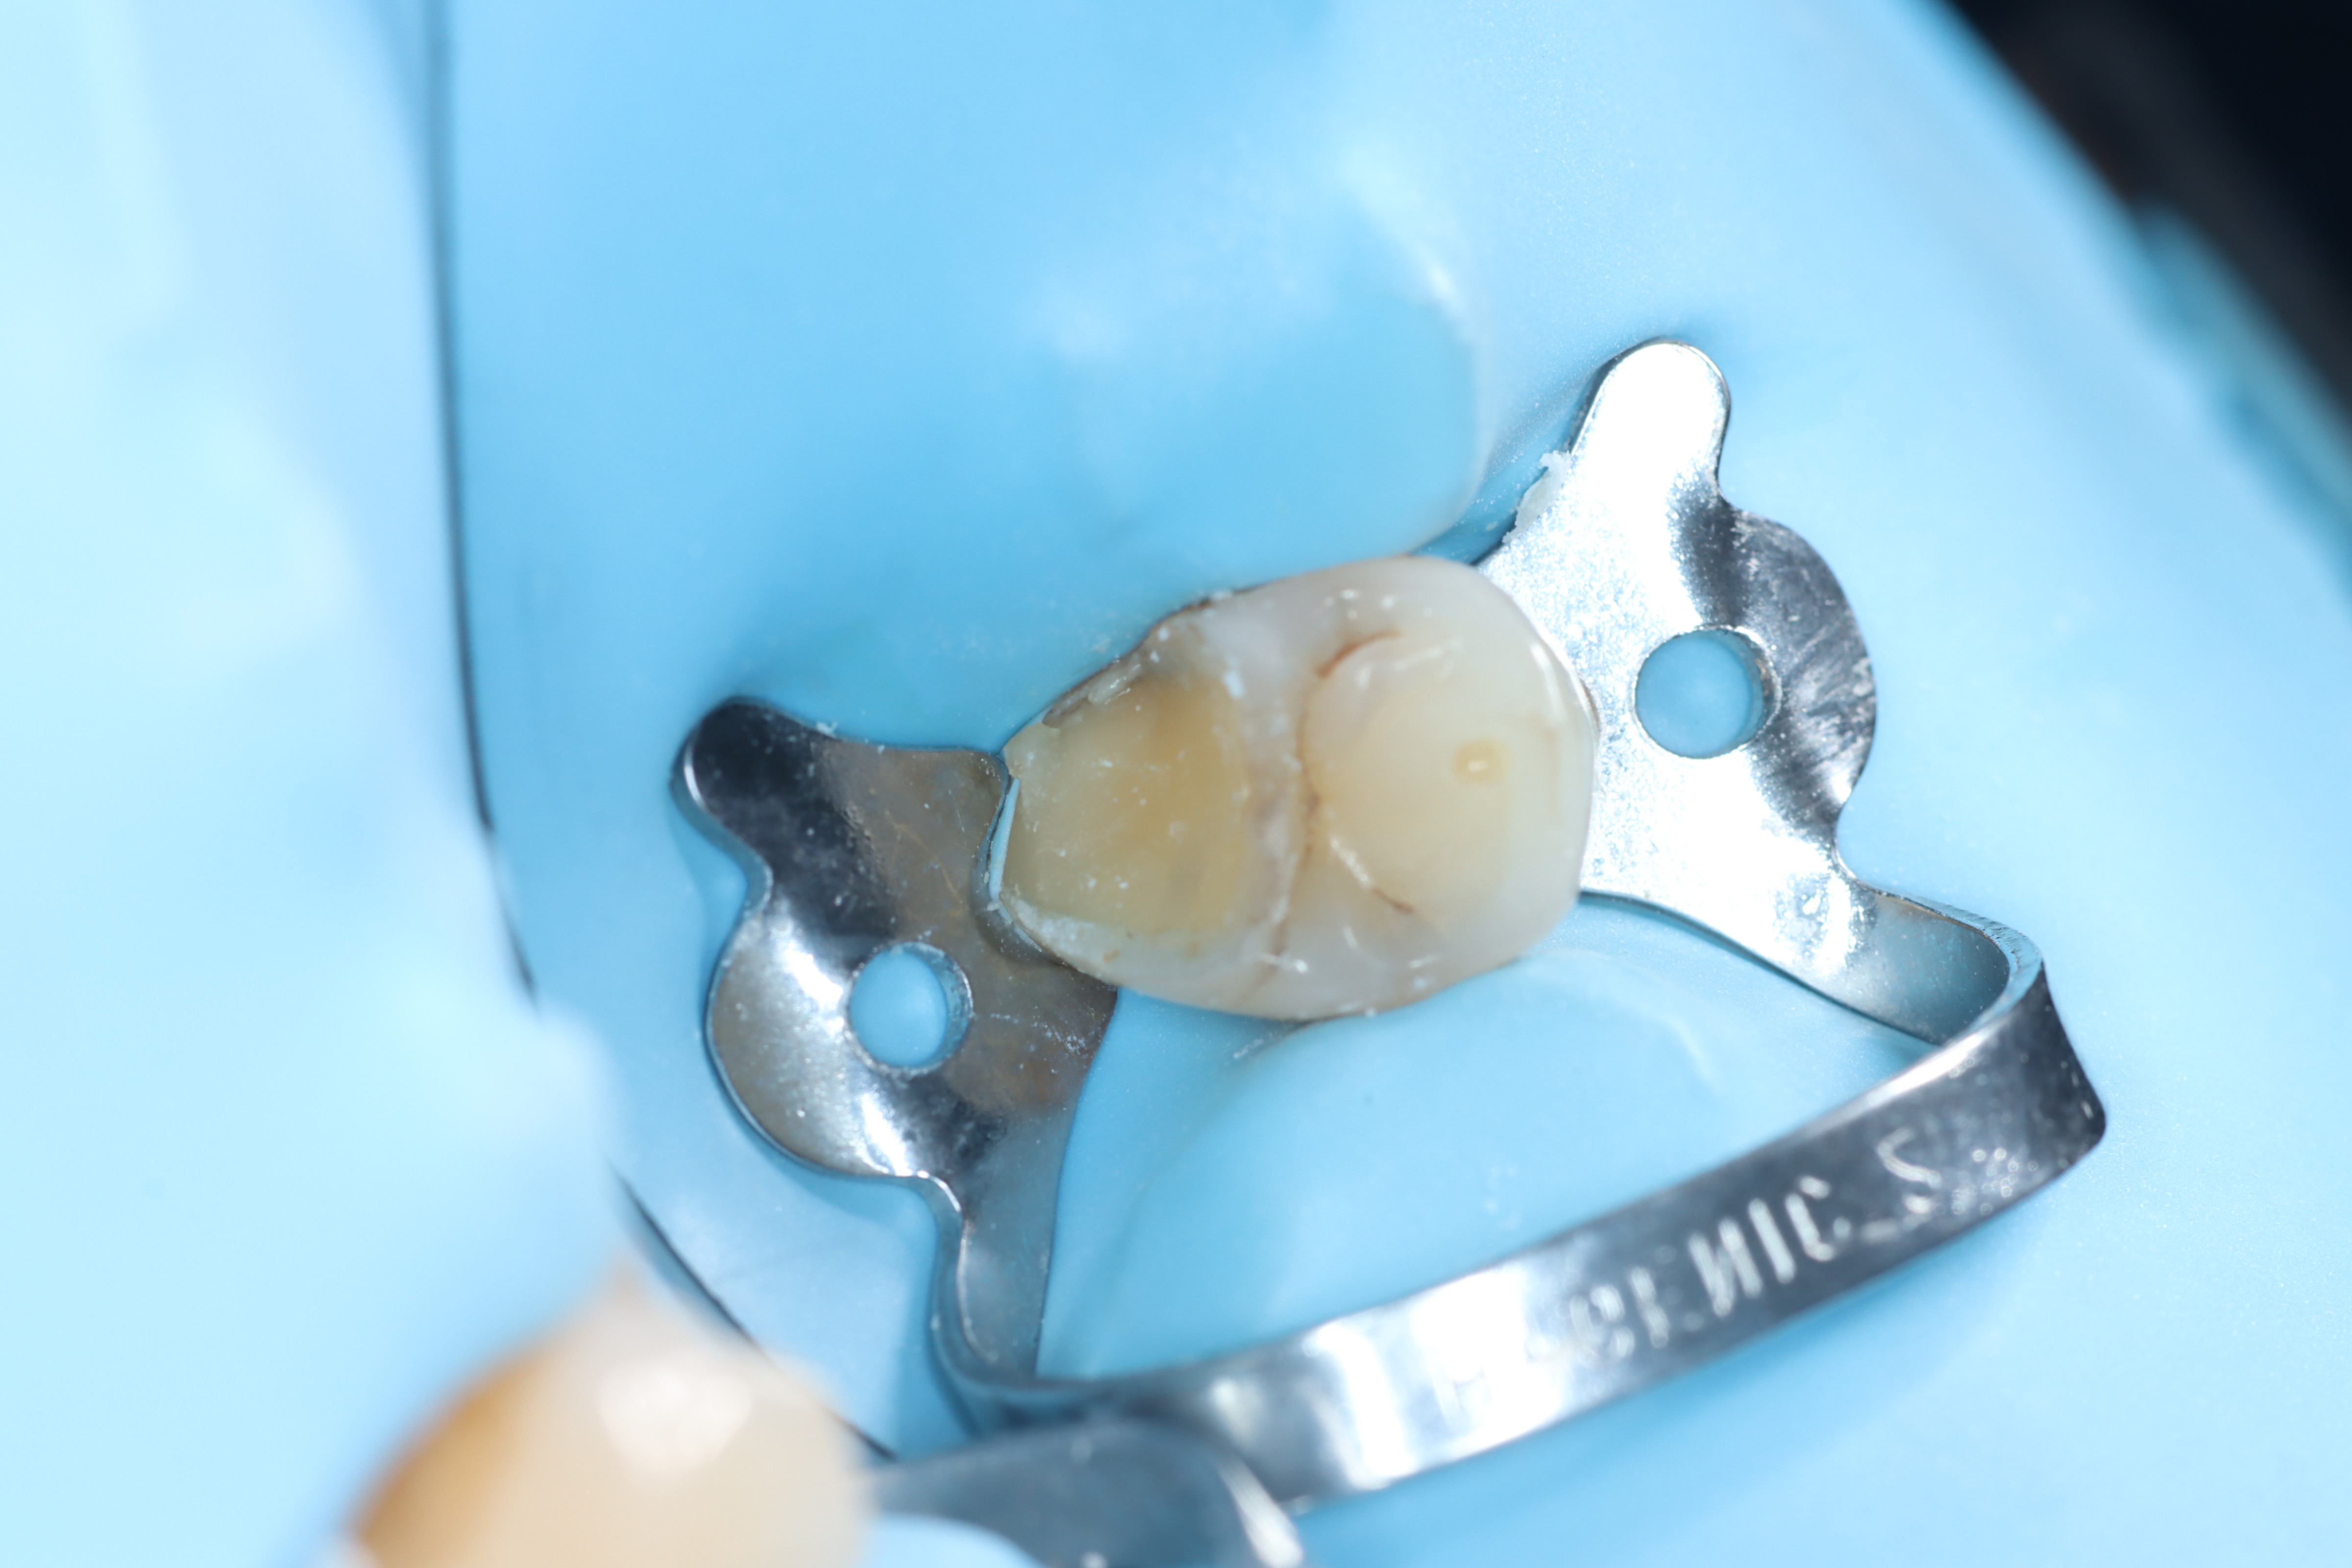

Case 6 – Periodontics

Crown lengthening Surgery on a premolar